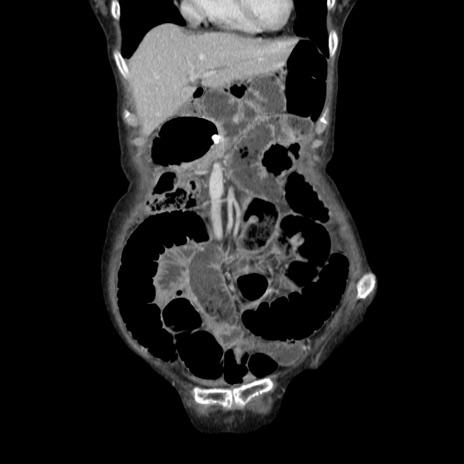

症例25(冠状断像)

【症例】80歳代女性

【主訴】胸のつかえ感

【現病歴】約9時間前に食後から胸のつかえた感じあり、嘔吐あり、来院。

【既往歴】胃癌(全摘)、胆摘、虫垂炎

【身体所見】心窩部に圧痛あり、反跳痛なし。

【データ】WBC 5700、CRP 0.05